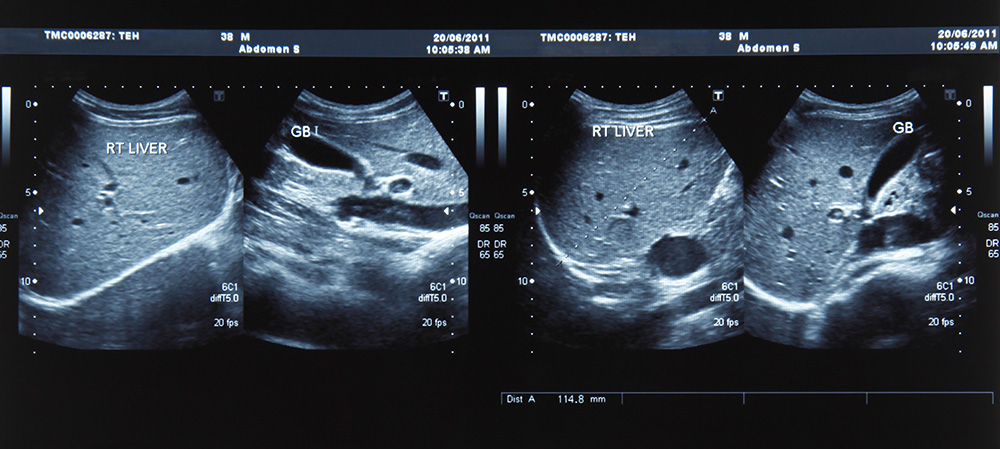

Provádíme sono/ultrazvuk vyšetření celého břicha (žlučníku, jater, slinivky, ledvin, moč. měchýře), uzlin a štítné žlázy. Vyšetření provádíme na přístroji TOSHIBA XSARIO.

Nevyšetřujeme sono/ultrazvuk prsou, kloubů, šlach, svalů, tepen, karotid, scrota.